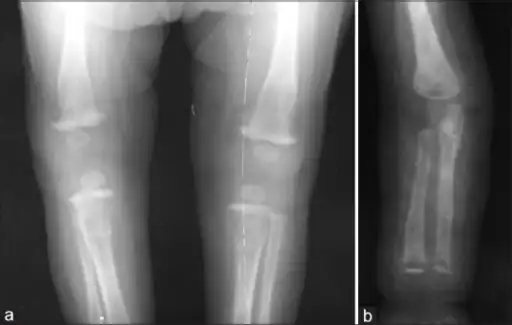

Refusal to move a limb in an infant may result from inflammation around bone or cartilage.[1]

Late onset features include deformity of the nose, lower legs, forehead, collar bone, jaw, and cheek bone.[1] Some of these bone defects can be detected early.[16] There may be a perforated or high arched palate, and recurrent joint disease.[1][4] Other late signs include scarred skin, intellectual disability, hydrocephalus, and juvenile general paresis.[1] Eighth nerve palsy, interstitial keratitis and small notched teeth may appear individually or together; known as Hutchinson triad.[1][18]